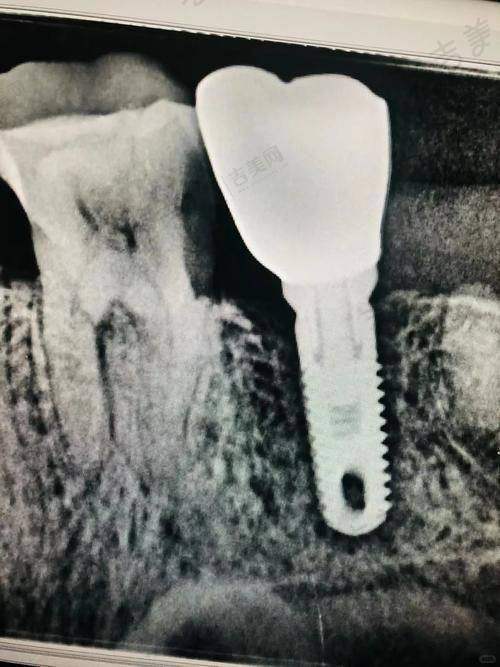

李孟奇医生顾客实例

虽然没有具体的顾客实例细节,但从患者评价可以推测,李孟奇医生在临床诊疗中取得了不错的成效。例如有患者对他做根管治疗的评价良好,说明他在牙体牙髓治疗方面技术娴熟,能为患者解决实际问题。在种植牙方面,他熟练掌握多种精良技术,如即刻种植和微创种植,这些技术的应用能为患者带来更好的治疗体验和成效,相信也有不少成功的种植牙实例。